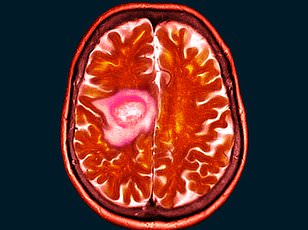

When Shelley Whittaker first noticed a persistent blur in her left eye, she assumed it was a simple matter of her mascara smudging or perhaps an issue with her contact lenses. The 47-year-old health and hygiene worker from Bolton, Greater Manchester, dismissed the symptom for months, even joking with friends about the possibility of going blind. But what began as a minor inconvenience quickly escalated into a life-altering diagnosis. In May 2025, after visiting an optician for a routine check-up, Whittaker was referred to an eye clinic, where scans revealed the presence of a rare benign brain tumor known as a spheno-orbital meningioma—roughly the size of a golf ball. The discovery marked the start of a harrowing journey that would upend her life and raise urgent questions about the safety of a widely used contraceptive.

According to the NHS, while there is no definitive causal relationship between Depo-Provera and meningiomas, prolonged use of medroxyprogesterone may slightly increase the risk of developing such tumors, though the condition remains rare. Whittaker's case, however, has sparked renewed scrutiny over the medication's safety profile. During her six-month recovery period following a 10-hour surgery to remove 90% of the tumor, she reflected on how her life had changed. "I never had any problems with the injection," she said. "The only risks I was warned about were weight gain and needing more calcium. I never imagined this." Her left eye had swelled dramatically due to the tumor's pressure on the optic nerve, a condition that could have led to permanent blindness if treatment had been delayed.

The surgical team emphasized the complexity of her case. The remaining 10% of the tumor could not be removed because it was too close to critical nerves, leaving Whittaker with a lifelong battle against the disease. "The surgeon told me there was no other option but surgery," she recalled. "It was a tough decision, but I had no choice." Her story has since prompted discussions among medical professionals about the need for clearer risk disclosures for patients on long-term hormonal contraceptives. While Depo-Provera remains a trusted method of birth control, Whittaker's experience highlights the importance of transparency in medication advisories and the value of early intervention when symptoms arise.